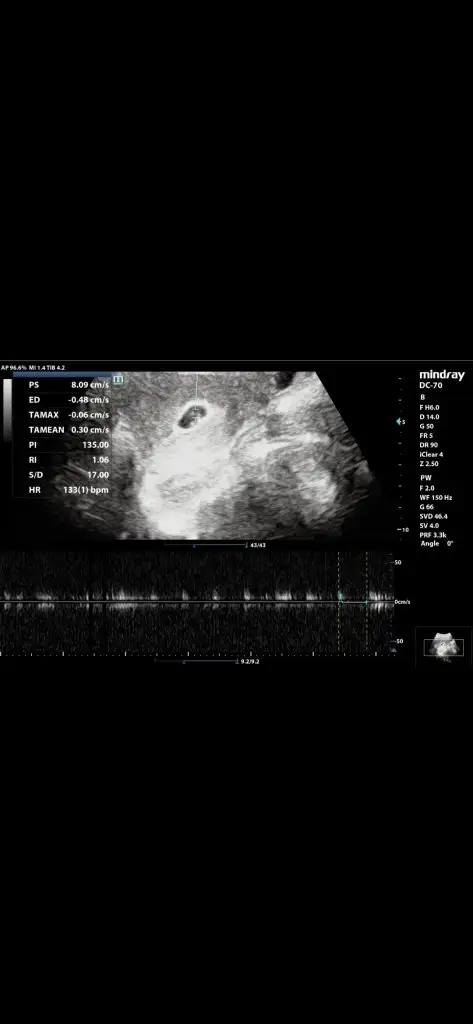

Kızlar bir tanıdığınız varsa veya doktorunuza sorabilir misiniz lütfen yardım edin. Bebeğimin katili olmak istemiyorumKızlar benim bir defa çok az parlak kırmızı kanamam gelmişti. Onunla acile gittim o gece ne kanama ne pembelik oldu bir daha. Sabahına uyuşmazlık iğnesi vurdular,beta 4300 çıktı gece sabah 4030 çıktı. Sabah doktor geldi baktı dedi ki kalp atışı ritmik, şu an iyi, kanama alanı yok. 3 saat sonra başka doktora gittim bebeğin yolk kesesi büyük normal kesesine göre, betan da aşırı düşük. Yüzde 99 düşer dedi ama benim dünden beri minicik çok çok açık pembe akıntıdan başka bir kanamam yine olmadı. Şu an uyandim yine kanamam yok. Böyle kanamasiz, ağrısız düşük olur mu. Biri öyle biri böyle dedi. Biri progestan kullan dedi. Diğeri de sadece düşüğü ertelersin dedi. Şu anda da 3. Doktor seçeneğim yok. Düşük riski varsa şehir değiştirmek de istemiyorum. Son görsel ilk doktorun sağlıklı diyen. Sonradan haftasını tekrar ölçtü 6+1 demişti Eki Görüntüle 3267882 Eki Görüntüle 3267886

Ben çok bilgili değilim bu konuda canım. Gebeliğimin ilk aylarında bende ufak bir kanama yaşamıştım doktorumu aradım hemen, o da sağlıklı bebek tutunur sağlıksız bebek tutunmaz vücut atar dedi. Bu söz çok canımı yaktı nolur tutunsun diye çok dua ettim her haliyle kabulüm dedim. Düşük riskim olmadı ama 37.haftada aniden kaybettim. Yaşadığım acı kaybetme korkusunun bin katıydı belki. Demek ki hata ettim en başta. Şimdi düşünüyorum rabbim veriyorsa da alıyorsa da vardır bir bildiği. Bebeğin sağlıklı ise ki İnşAllah sağlıklıdır senle kalır değilse annesinin vücudunu temizleyerek yeni gebeliğe daha sağlıklı hale getirerek cennette beklemeye gider. Yaşadığın bu belirsizlikte İnşAllah en kısa sürede netliğe kavuşurKızlar benim bir defa çok az parlak kırmızı kanamam gelmişti. Onunla acile gittim o gece ne kanama ne pembelik oldu bir daha. Sabahına uyuşmazlık iğnesi vurdular,beta 4300 çıktı gece sabah 4030 çıktı. Sabah doktor geldi baktı dedi ki kalp atışı ritmik, şu an iyi, kanama alanı yok. 3 saat sonra başka doktora gittim bebeğin yolk kesesi büyük normal kesesine göre, betan da aşırı düşük. Yüzde 99 düşer dedi ama benim dünden beri minicik çok çok açık pembe akıntıdan başka bir kanamam yine olmadı. Şu an uyandim yine kanamam yok. Böyle kanamasiz, ağrısız düşük olur mu. Biri öyle biri böyle dedi. Biri progestan kullan dedi. Diğeri de sadece düşüğü ertelersin dedi. Şu anda da 3. Doktor seçeneğim yok. Düşük riski varsa şehir değiştirmek de istemiyorum. Son görsel ilk doktorun sağlıklı diyen. Sonradan haftasını tekrar ölçtü 6+1 demişti Eki Görüntüle 3267882 Eki Görüntüle 3267886

Bence için rahat olsun istiyorsan bir başka doktora da git..belkide kalb atışı durmuş..ben kalb atışı durmadan sona kadar bekledim..resimle kimse bir şey söyleyemez canımKızlar benim bir defa çok az parlak kırmızı kanamam gelmişti. Onunla acile gittim o gece ne kanama ne pembelik oldu bir daha. Sabahına uyuşmazlık iğnesi vurdular,beta 4300 çıktı gece sabah 4030 çıktı. Sabah doktor geldi baktı dedi ki kalp atışı ritmik, şu an iyi, kanama alanı yok. 3 saat sonra başka doktora gittim bebeğin yolk kesesi büyük normal kesesine göre, betan da aşırı düşük. Yüzde 99 düşer dedi ama benim dünden beri minicik çok çok açık pembe akıntıdan başka bir kanamam yine olmadı. Şu an uyandim yine kanamam yok. Böyle kanamasiz, ağrısız düşük olur mu. Biri öyle biri böyle dedi. Biri progestan kullan dedi. Diğeri de sadece düşüğü ertelersin dedi. Şu anda da 3. Doktor seçeneğim yok. Düşük riski varsa şehir değiştirmek de istemiyorum. Son görsel ilk doktorun sağlıklı diyen. Sonradan haftasını tekrar ölçtü 6+1 demişti Eki Görüntüle 3267882 Eki Görüntüle 3267886